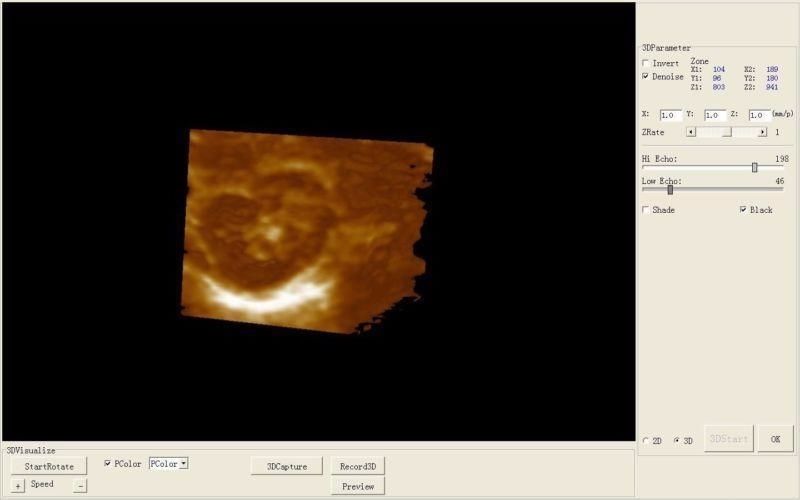

Comprehensive Diagnostic Capabilities

The Laptop Ultrasound Scanner is designed to provide clear and precise imaging, making it an essential tool for healthcare professionals. This device offers advanced functionality, allowing doctors to perform a wide range of examinations. Because it includes a transvaginal probe, it is particularly effective for gynecological assessments, ensuring accurate diagnosis.

The Laptop Ultrasound Scanner is equipped with an intuitive interface that simplifies operation. Even those who may not be tech-savvy will find it easy to navigate through various functionalities. Additionally, the visual output on the laptop screen is clear and informative. So, both experienced and novice users can quickly learn how to use the device effectively.